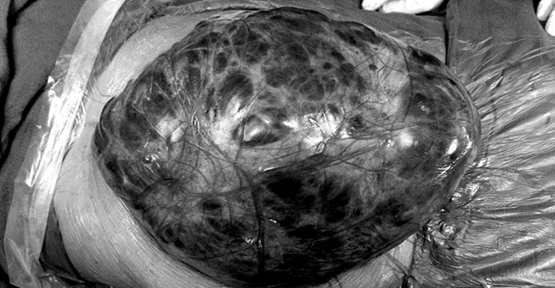

Hindistan'da, en ağır ameliyatlara bile alışık olan doktorları şaşkına çeviren bir olay yaşandı. Yeni Delhi'de yaşayan 35 yaşındaki kadının böbreğinden, yaklaşık 7 kilo ağırlığında ve futbol toğu görünümünde bir tümör alındı. Kadının hastaneye 'karın ağrısı' şikayetiyle geldiğini kaydeden doktorlar, tümörün böbreği neredeyse patlatma seviyesine getirdiğini, büyük ölçüde böbreğe zarar verdiğini söyledi.

Daily Mail'de yer alan habere göre, ismi açıklanmayan Hintli kadın kilo aldığını sandığını, testler yapılıncaya kadar hiçbir şey anlamadığını kaydetti.

6 saat süren operasyonun ardından açıklama yapan doktorlar, kadının hayatta kalmasının bile bir mucize olduğunu, ameliyat esnasında büyümeyi bekleyen 3 tümöre daha rastladıklarını ve onları da alarak talihsiz kadının hayatını kurtardıklarını ifade ettiler.

Operasyonu gerçekleştiren Doktor Hardev Singh Bhatyal, bu büyüklükteki tümörlerin acilen alınması gerektiğini ifade ederek, bu tür vakalarda doktorların genel olarak tümörle beraber tüm böbreği aldığını ve bu tür ağır hastalıklarda böbreği muhafaza etmenin çok zor olduğunu vurgulayarak, böbreği destekleyen hayati kan damarlarını kurtardıklarını ve bu esbeple böbreğin tamamını almadıklarını kaydetti.